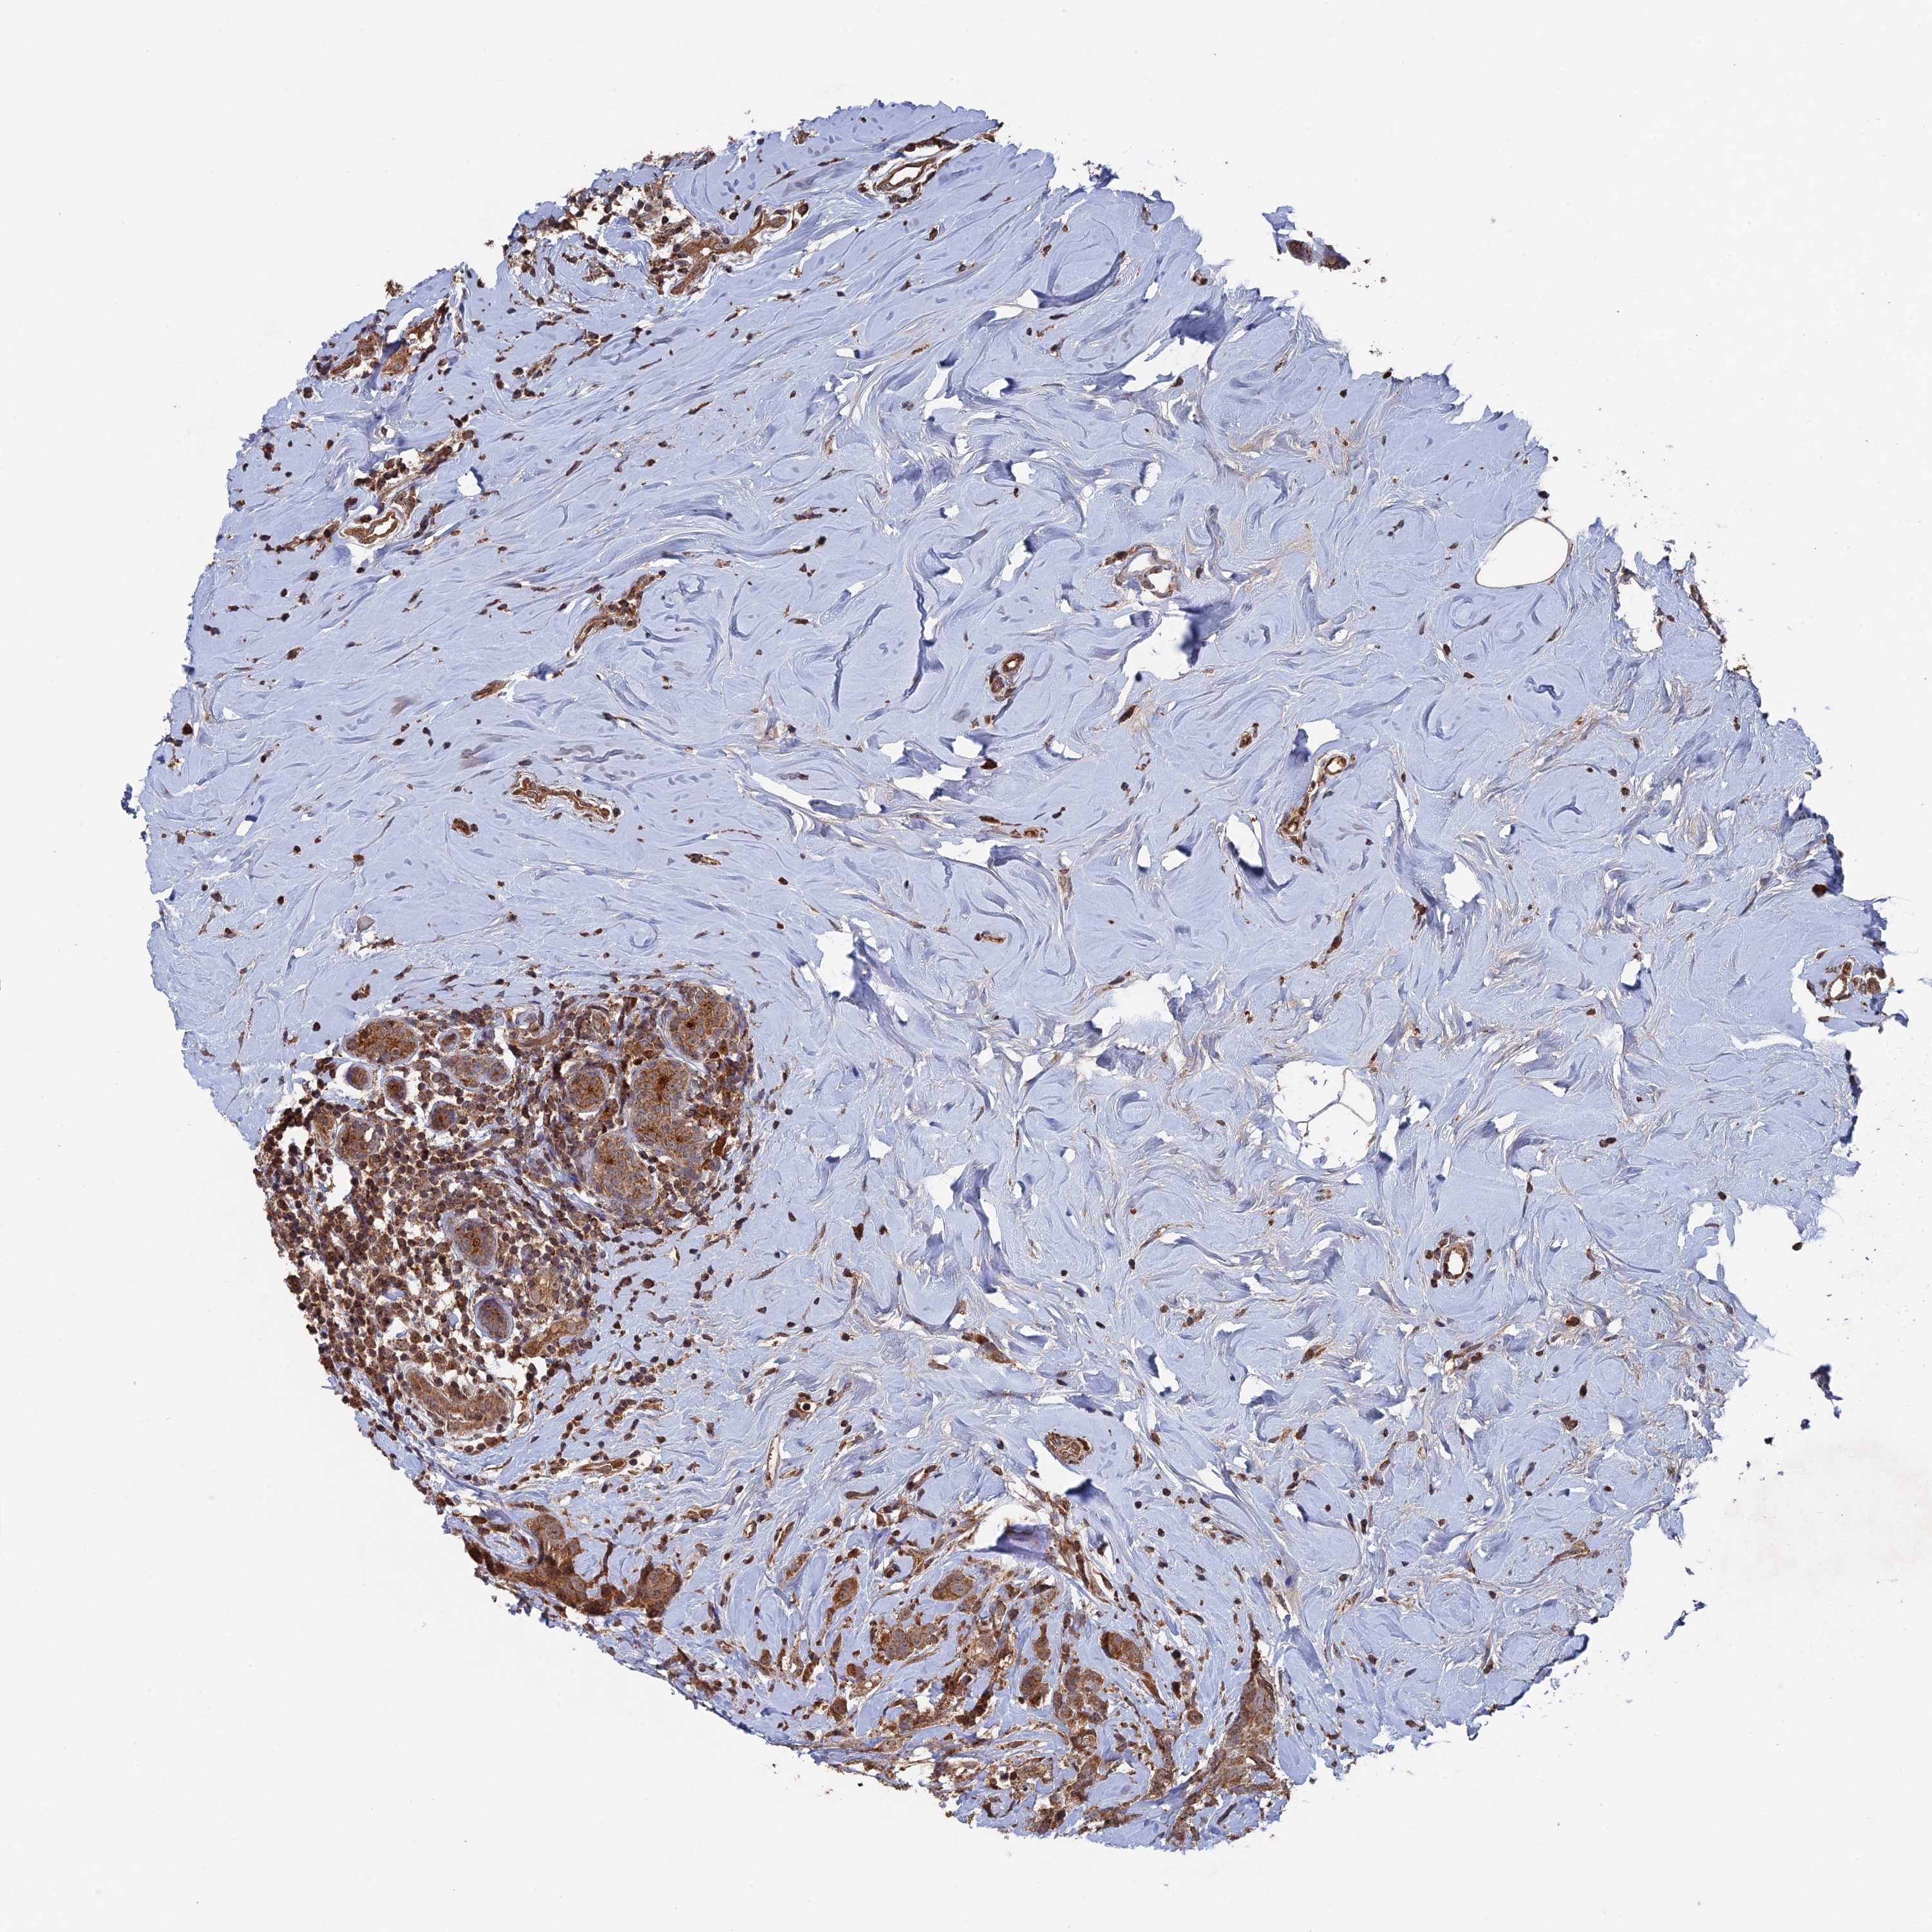

CANCER BREAST CANCER Show tissue menu

BRCA TCGA BRCA VALIDATION PROTEIN EXPRESSION

Breast cancer

Human cancer

RAB15 is not prognostic in Breast Invasive Carcinoma (TCGA)